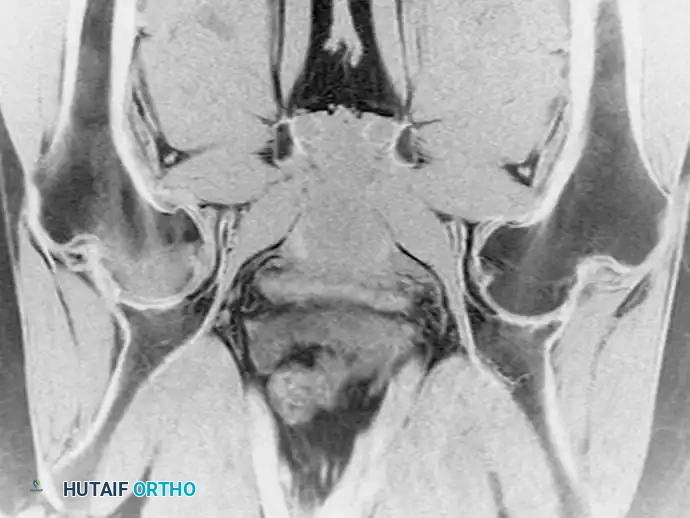

لا تقتصر قوة الرنين المغناطيسي على مفصل الورك فحسب، بل تمتد لتشمل المفاصل الأخرى كالركبة، مما يثبت فعالية هذه التقنية في كشف أدق التفاصيل التشريحية والمرضية في العظام والغضاريف. نستعرض هنا بعض الأمثلة التي توضح دقة الرنين المغناطيسي في تشخيص إصابات المفاصل:

هذه الصور تؤكد بما لا يدع مجالا للشك أن الاعتماد على الرنين المغناطيسي يوفر خريطة طريق واضحة للطبيب المعالج، سواء كان يتعامل مع كيس زلالي، أو كدمة عظمية، أو كسر خفي في صفيحة النمو، أو آفة غضروفية، مما ينعكس إيجابا على دقة التشخيص في مفصل الورك والمفاصل الأخرى.